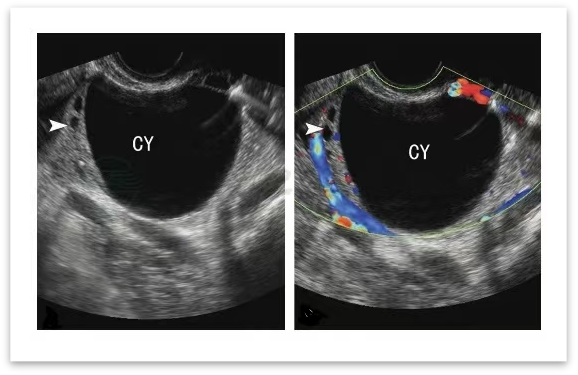

✅揪出「隐形问题」:有些情况肉眼无法察觉,比如卵泡长到一定程度却不破裂(未破裂卵泡黄素化综合征),或者卵泡没长够大小就提前排出。这些问题都会影响受孕,而动态监测能及时发现异常,为医生调整方案提供依据。

▲小卵泡排卵